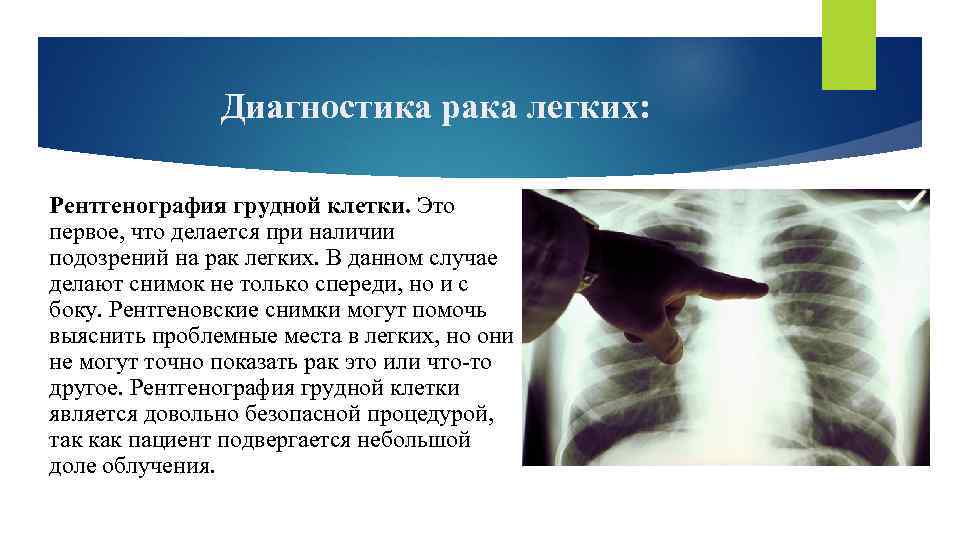

Диагностика рака легких: Рентгенография грудной клетки. Это первое, что делается при наличии подозрений на рак легких. В данном случае делают снимок не только спереди, но и с боку. Рентгеновские снимки могут помочь выяснить проблемные места в легких, но они не могут точно показать рак это или что-то другое. Рентгенография грудной клетки является довольно безопасной процедурой, так как пациент подвергается небольшой доле облучения.

Диагностика рака легких: Рентгенография грудной клетки. Это первое, что делается при наличии подозрений на рак легких. В данном случае делают снимок не только спереди, но и с боку. Рентгеновские снимки могут помочь выяснить проблемные места в легких, но они не могут точно показать рак это или что-то другое. Рентгенография грудной клетки является довольно безопасной процедурой, так как пациент подвергается небольшой доле облучения.